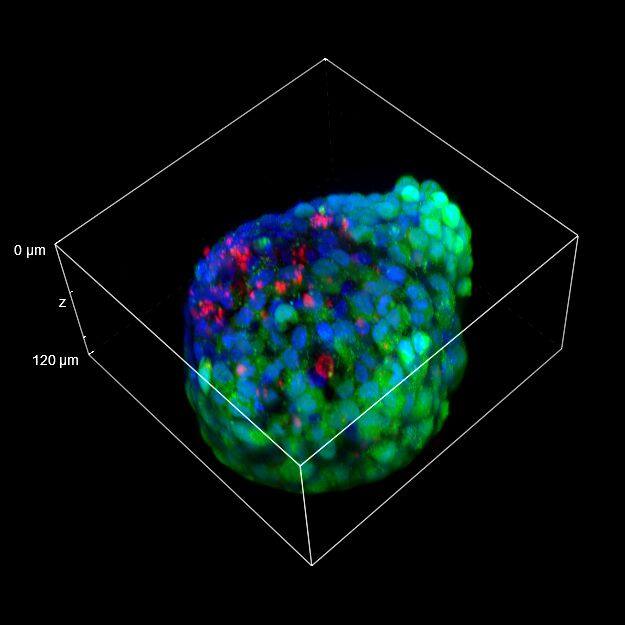

为了更好地理解 3D 细胞组织,在图 C 中,我们展示了使用两种物镜获得的同一球体的体积视图(120 um 厚),甚至在 3D 肿瘤球体的更深区域也能看到染色。最后,在 图 D 中,显示了使用 25 倍硅油物镜获得的整个球体的 3D 电影特效。

图 C:使用 20 倍空气物镜(左)和 25 倍硅油物镜(右)获得的球体的 3D 体积视图。活细胞用钙黄绿素(绿色)标记,死细胞用 PI(红色)标记。细胞核用 Hoechst(蓝色)染色。沿 Z 轴的比例尺:120 um。这些图像是使用 CrestOptics X-Light V3 转盘获取的。